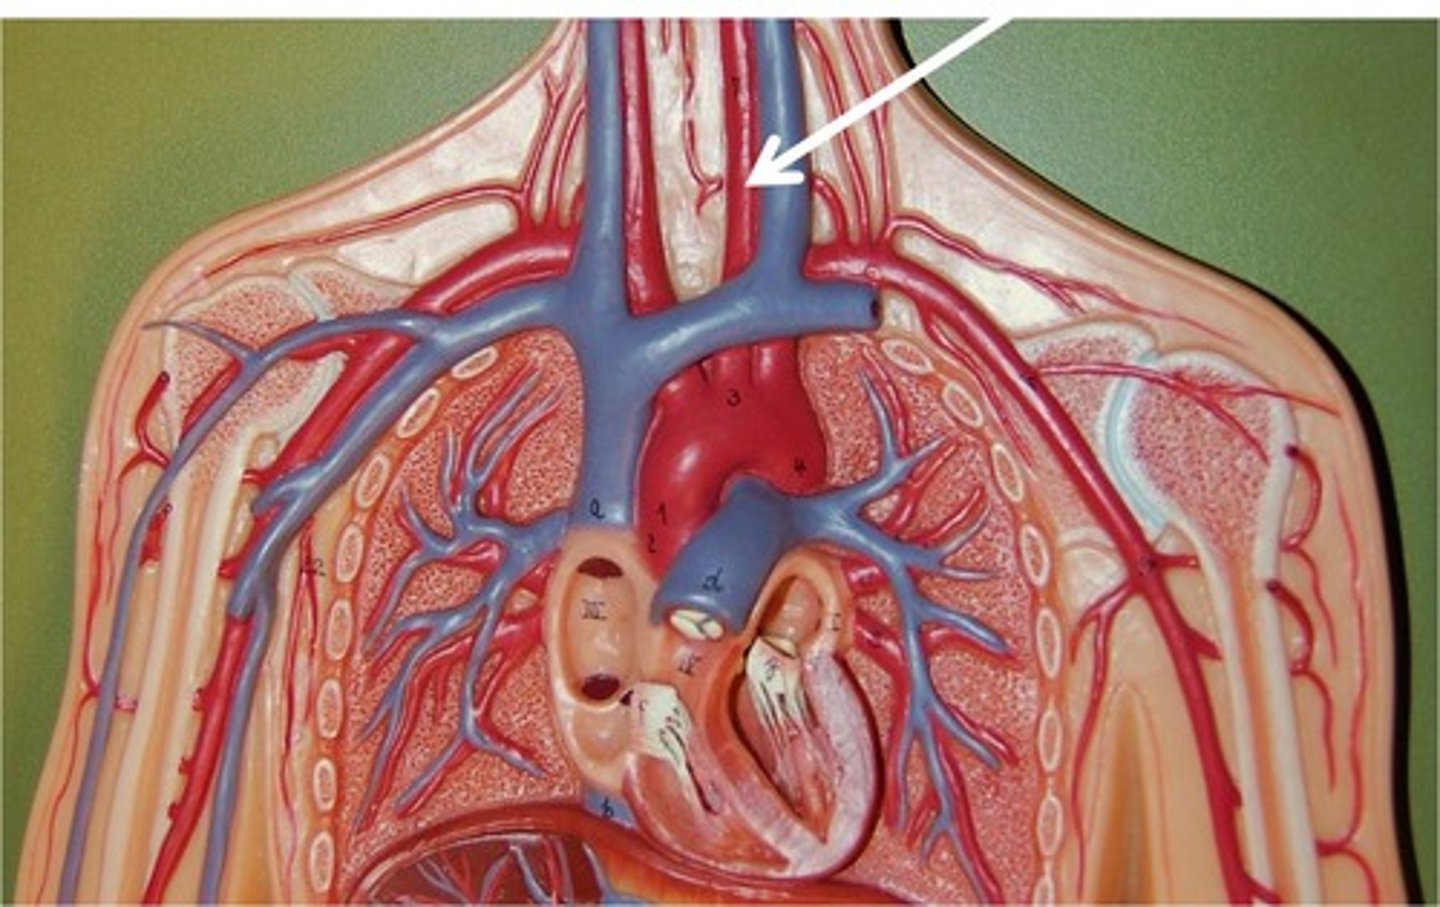

superior vena cava

brachiocephalic vein

subclavian vein

aortic arch

ascending aorta

brachiocephalic artery